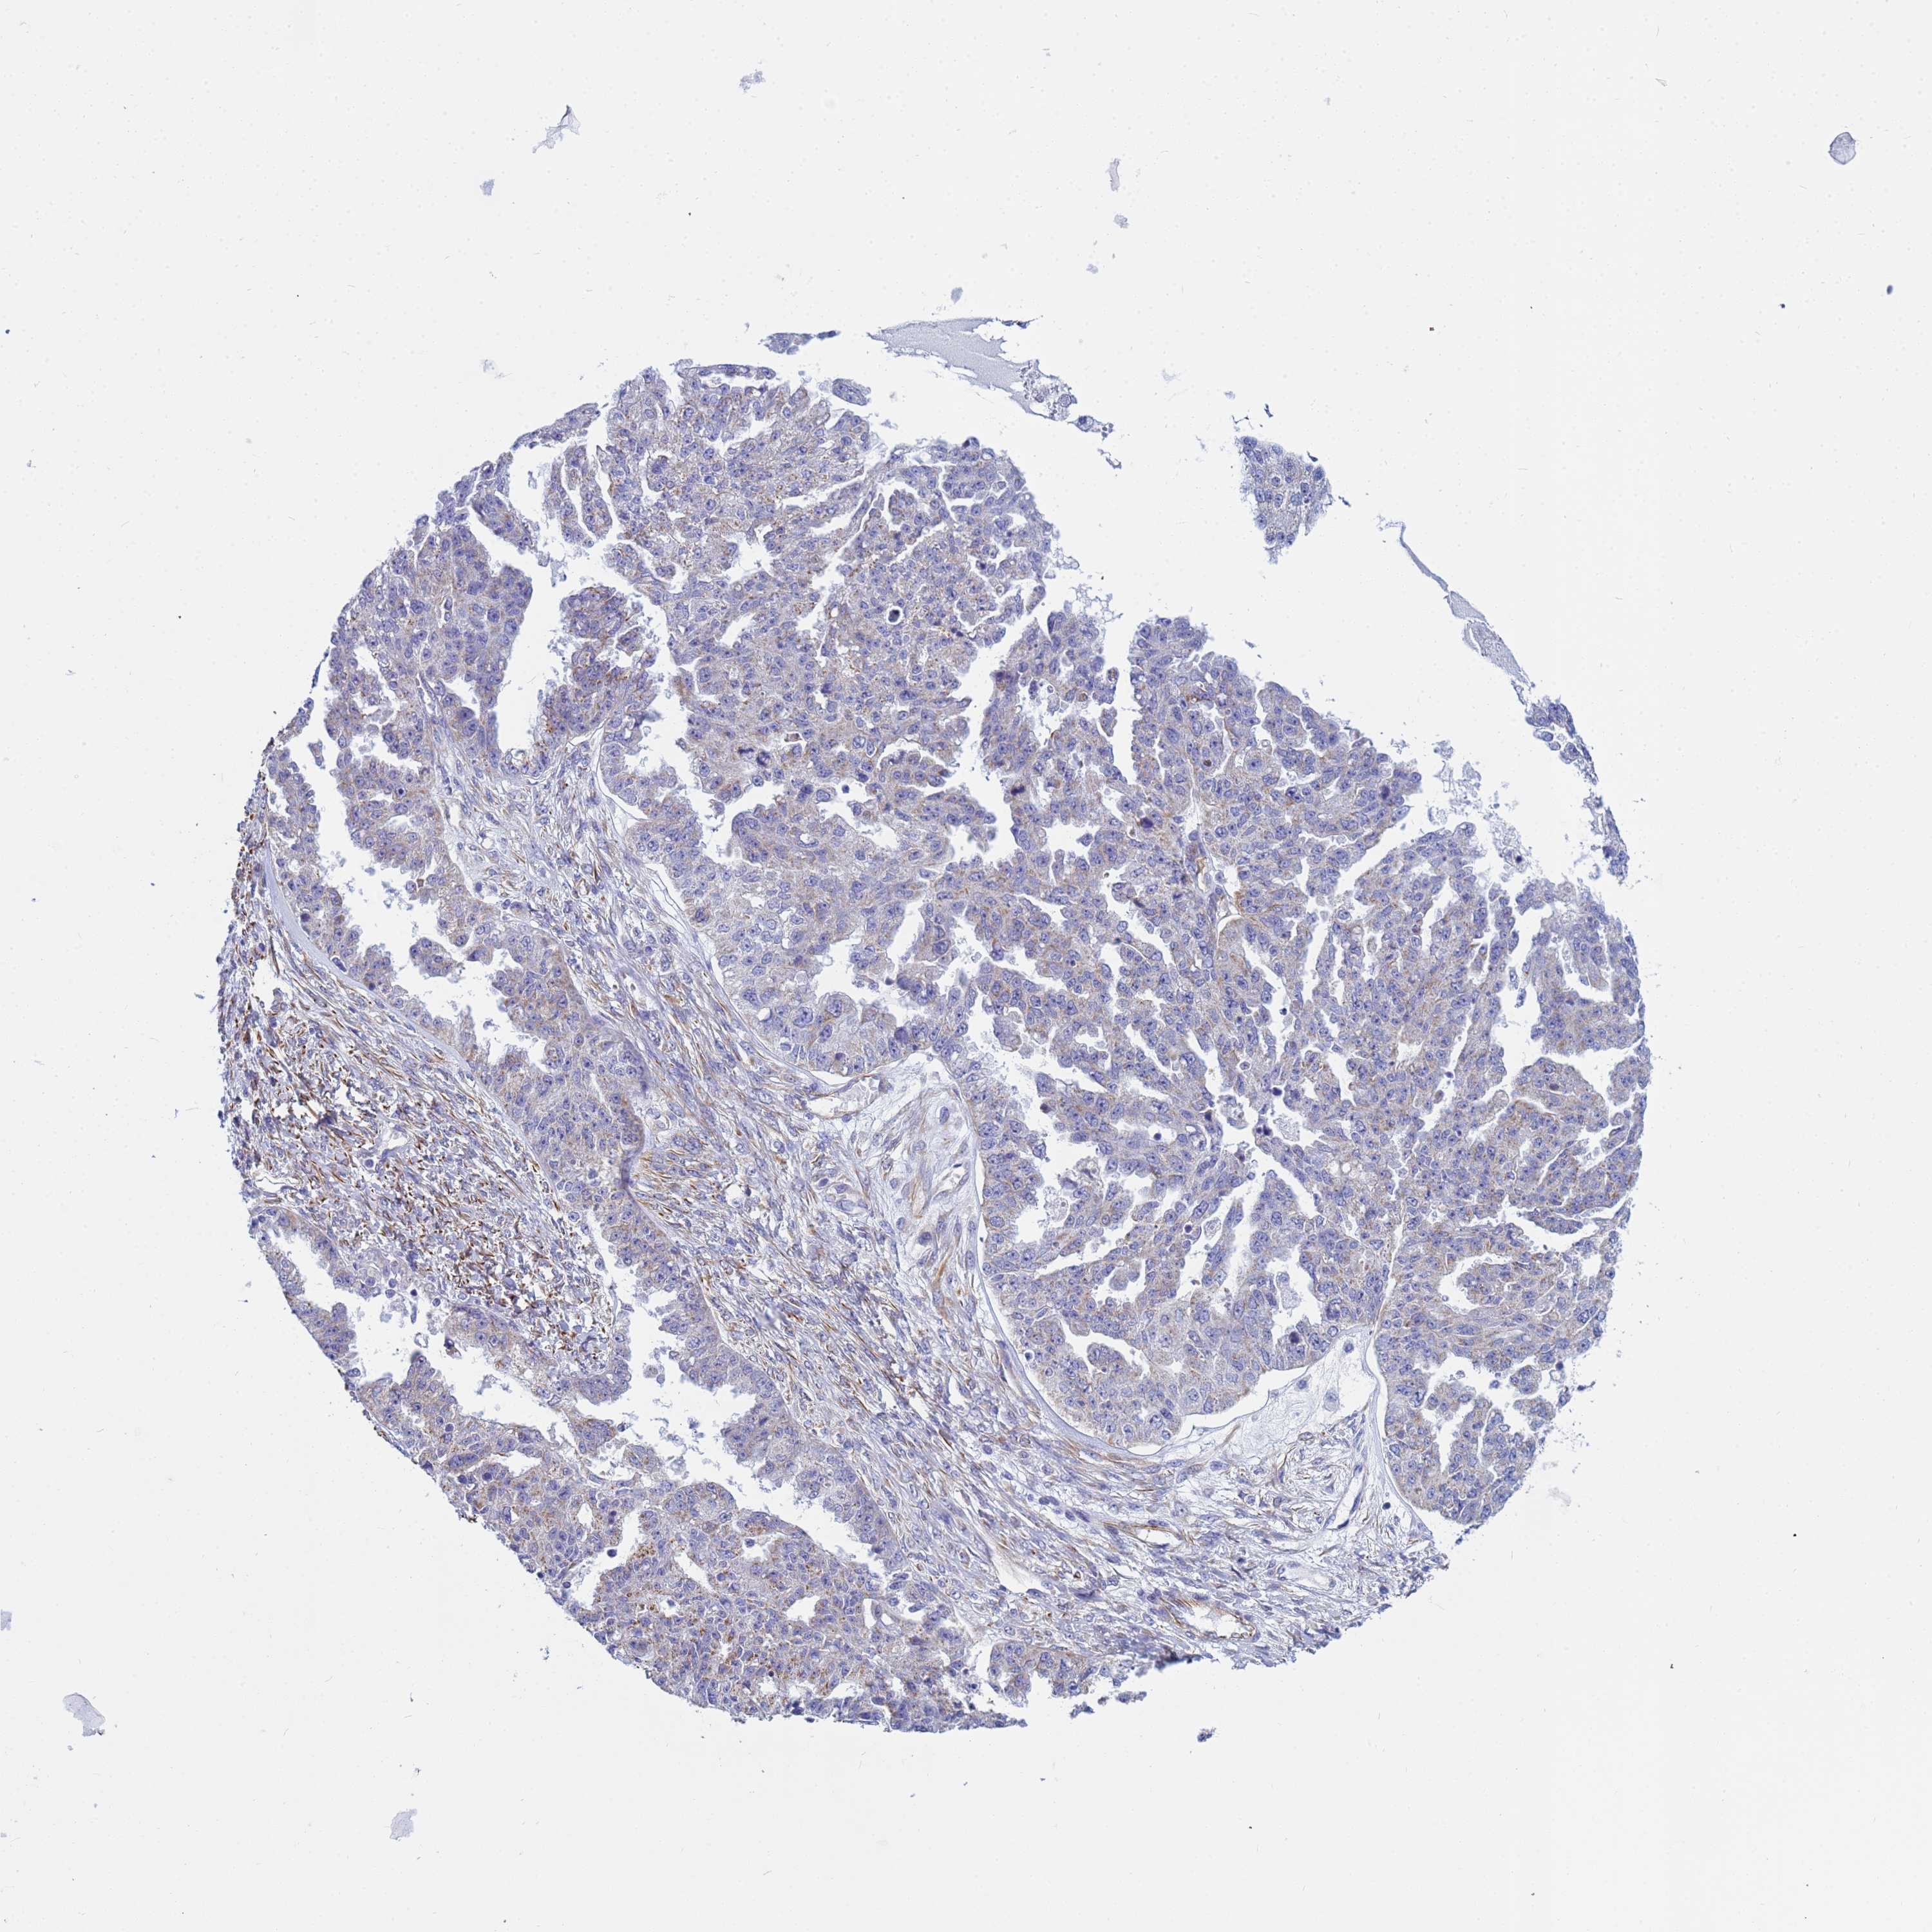

OVARIAN CANCER - Protein expressioni

A mouse-over function shows sample information and annotation data. Click on an image to view it in a full screen mode. Samples can be filtered based on level of antibody staining by selecting one or several of the following categories: high, medium, low and not detected. The assay and annotation is described here.

Note that samples used for immunohistochemistry by the Human Protein Atlas do not correspond to samples in the TCGA dataset.

Antibody stainingi

Antibody staining in the annotated cell types in the current human tissue is reported as not detected, low, medium, or high, based on conventional immunohistochemistry profiling in selected tissues. This score is based on the combination of the staining intensity and fraction of stained cells.

Each image is clickable and will lead to virtual microscopy that enables deeper exploration of all samples and also displays staining intensity scores, fraction scores and subcellular localization as well as patient and tissue information for each sample.

Antibody HPA045278

Staining

High

Medium

Low

Not detected

Intensity

Strong

Moderate

Weak

Negative

Quantity

>75%

75%-25%

<25%

None

Location

Nuclear

Cytoplasmic/membranous

Cytoplasmic/membranous,nuclear

Cystadenocarcinoma, serous, NOS

Carcinoma, endometroid

Cystadenocarcinoma, mucinous, NOS

Carcinoma, NOS